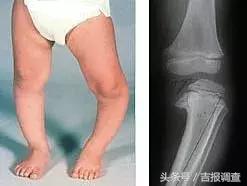

“O型腿” ,即俗称的“罗圈腿”,这种腿部畸形在医学上也叫做“膝内翻”,主要表现为孩子并脚站立时,双膝不能靠拢,两条腿向外侧弯曲,形成个“O”形。

“X型腿” ,即俗称的“碰膝症”,这种腿部畸形在医学上也叫做“膝外翻”,主要表现为孩子双膝并拢站立时,双脚不能并在一起,两小腿以膝盖为中心,向两侧撇开,形成个“X”形。

1岁之前的宝宝是O型腿,2岁以后逐渐变成X型腿,到4-5岁左右、X程度往往最明显,6岁以后X型弧度逐渐减小,7-8岁左右时双腿长成和成人一样的外观。

宝宝在妈妈子宫里时,整个身体呈蜷缩状,双腿和双脚都是环形、呈“O”型形状,在出生后的一段时间内仍旧会保持这种弧度。

病理性O型腿则需要尽早治疗,如佝偻病,先天性甲状腺功能降低导致钙磷代谢的异常,也会导致“O型腿”。